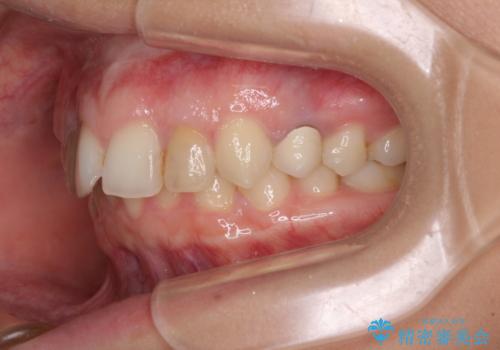

- 前歯の歯並びと神経を取って変色してしまった前歯を気にして来院された患者様です。

上下前歯の歯列不正はインビザラインにより整え、その後に、前歯2本をオールセラミッククラウンにて補綴治療することとしました。

下顎前歯が1本欠損しており、下顎歯列の大きさが本来よりも小さいため、上顎歯列とのバランスが悪く、深い咬み合わせになっていました。

上顎にIPRを多用して歯列の大きさを小さくするよう試みましたが、理想的な咬み合わせまでには改善させることはできませんでした。